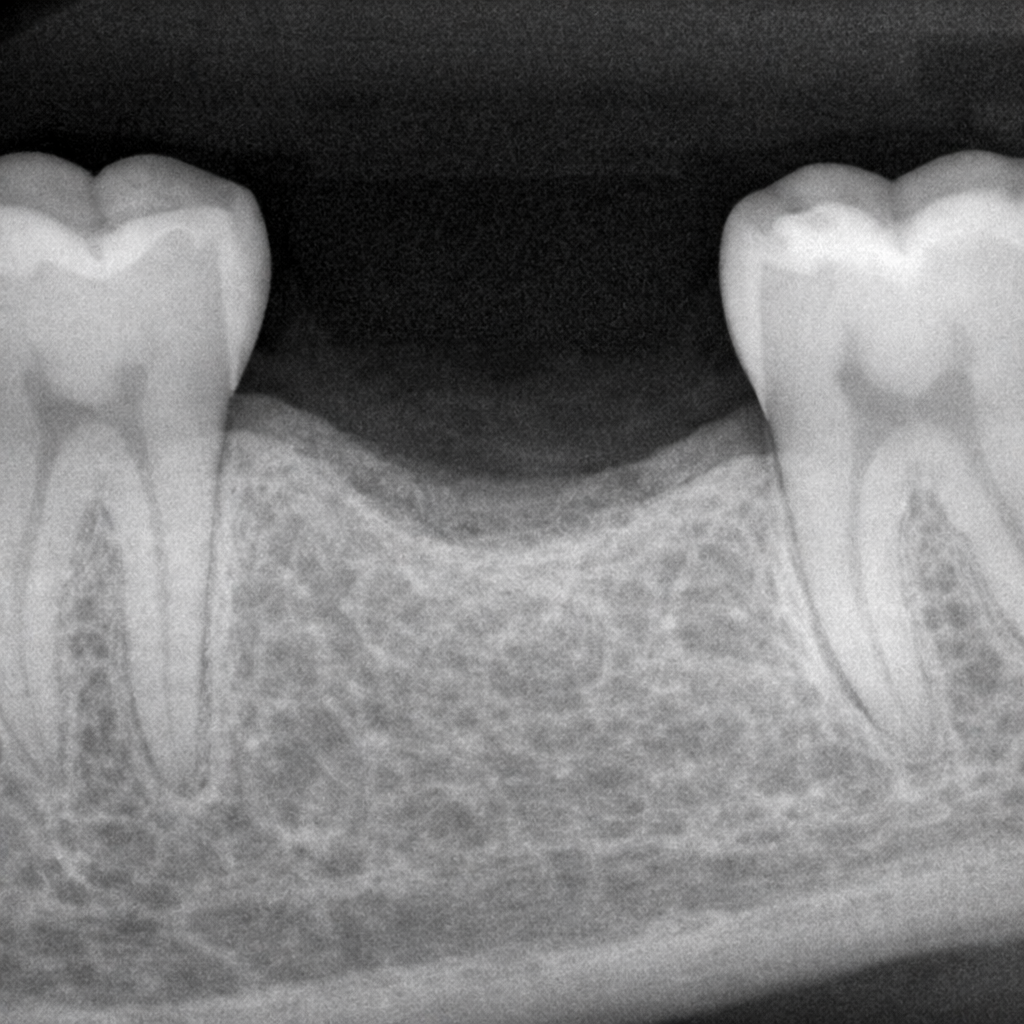

“치아 추출 후 첫 6~7개월 이내에 협설측 치조골 폭경의 약 29~63%가 감소하며, 이는 임플란트 식립을 위한 최적의 시기를 결정하는 핵심 요인이 됩니다.”

• 급격한 초기 골 흡수: 발치 후 초기 3~6개월 동안 가장 빠른 속도로 골 폭경이 감소하며, 이후에는 점진적인 감소세로 접어듭니다.

• 수평적 골 손실의 심각성: 6개월 시점에서 **수평적 폭경 감소(약 3.79mm)**는 수직적 높이 감소(약 1.24mm)보다 훨씬 더 현저하게 나타납니다.

• 광범위한 골 손실의 수치화: 발치 부위를 다시 열어 확인했을 때(Re-entry), 6개월 만에 수평적으로는 최대 63%, 수직적으로는 11~22%의 뼈가 소실됨을 확인했습니다.

결론 : 치아 발치 후 발생하는 치조골의 위축은 초기 3~6개월에 집중되므로, 치조골의 입체적 구조가 더 무너지기 전 조기 수복 및 적절한 치료 계획 수립이 임플란트의 성공률을 높이는 유일한 방법입니다.